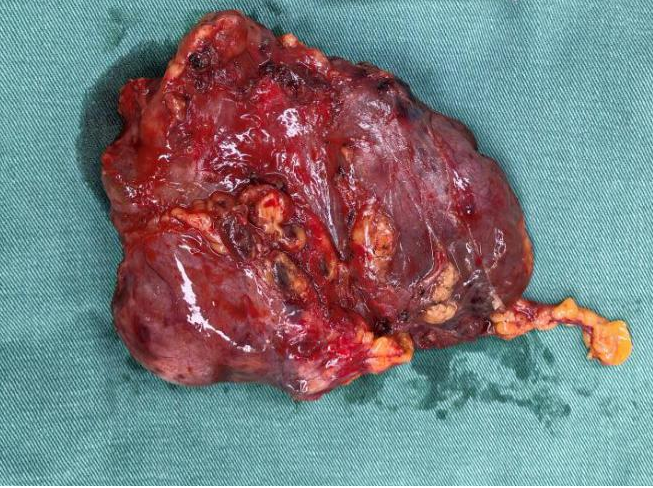

被切除的腫瘤

術前胸心血管外科團隊聯合多學科評估風險,確定手術方式、風險防范與圍手術期應急方案。術中,胸心血管外科副主任呂忠柱主任醫師主刀,通過正中胸骨切開手術,憑借精準操作避開致命陷阱,成功拆除前縱隔巨大腫瘤、完成胸腺擴大切除,同時清掃了周圍淋巴結,在保證安全的前提下達到了R0切除。手術過程順利,術后患者順利脫機拔管,已順利康復出院。